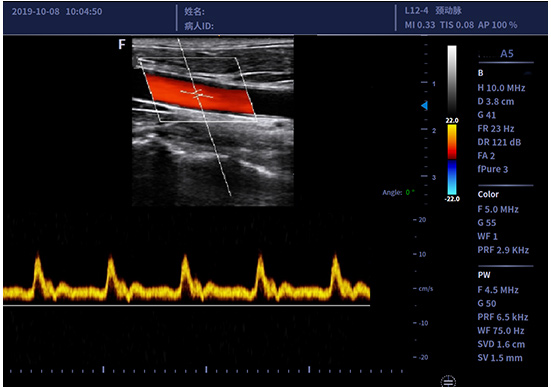

• L12-4/L12-5线阵探头

适用于外周血管、小器官、神经肌骨等

临床超声检查

自适应血流技术